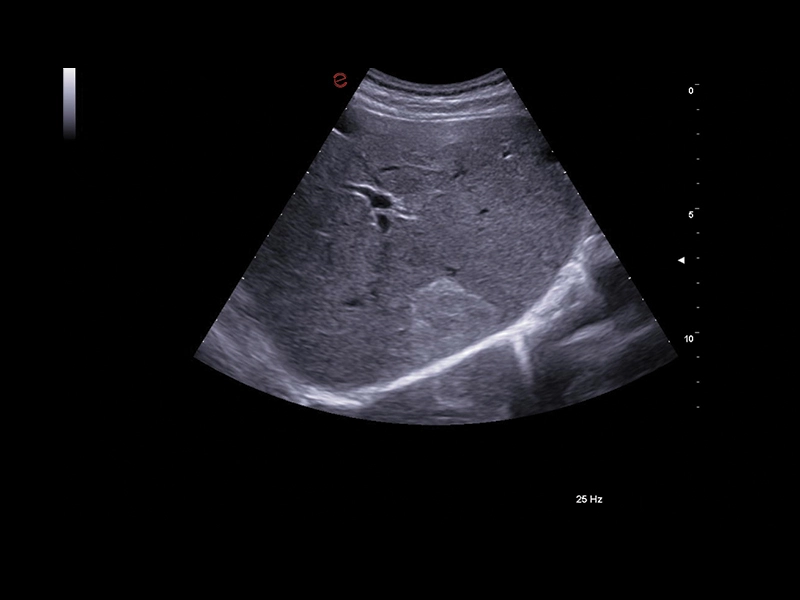

MyLab™X9 - Liver 01

MyLab™X9 - Liver 01

MyLab™X9 - Liver 02

MyLab™X9 - Liver 02

MyLab™X9 - Liver 03

MyLab™X9 - Liver 03

MyLab™X9 - Liver 04

MyLab™X9 - Liver 04

MyLab™X9 - Liver 05

MyLab™X9 - Liver 05